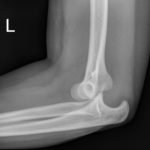

Elbow dislocations are classified by the position of the radio-ulnar joint relative to the humerus.1 Images 1, 2, and 3 show a left posterior elbow dislocation; the radius and ulna are displaced posteriorly with respect to the distal humerus. The lateral view of the elbow most clearly shows this: trochlear notch of the ulna is empty and displaced posteriorly relative to the trochlea. There is no associated fracture. Images 4 and 5 show the elbow status-post reduction, demonstrating proper alignment of the distal humerus with the radius and ulna.